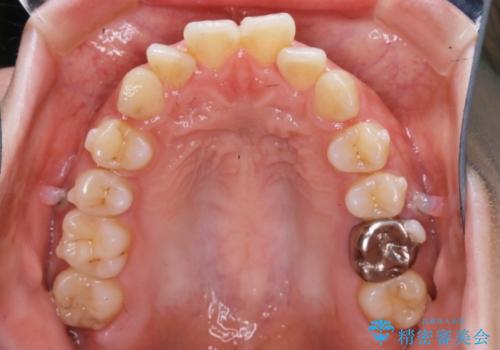

【非抜歯】インビザラインでガタつきと口元を改善!非抜歯でも印象が変わる矯正治療

- 歯のガタつきと口元の突出感を主訴に来院されました。

装置の希望がインビザラインだったため、非抜歯でインビザラインの特徴を最大限に生かして行う矯正治療を選択しました。

一般的に口元を下げるための治療というと抜歯矯正を思い浮かべる方が多いかと思います。そもそもガタつきを治したり歯を引っ込めるためのスペースの作り方には大きく分けて4種類の方法があります。

①抜歯 ②歯列の幅の拡大 ③IPR(歯の幅を削って小さくする) ④歯の後方移動 です。

インビザラインの登場により抜歯以外の3種類の方法を効率よく活用することができるようになりました。

そのため、非抜歯でも口元の環境が改善するケースがあります。